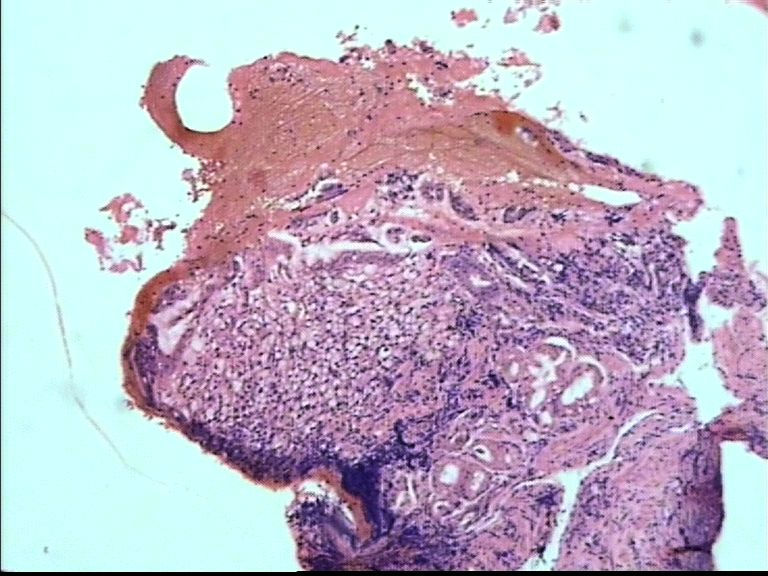

胃部溃疡3cm 53岁 男

仅此局部形态,应该是印戒细胞癌,最好有更多的背景资料

印戒细胞癌

倾向印戒细胞癌

诊断印戒细胞癌

印戒细胞癌高度可疑,建议做:CK、CD68、PAS帮助诊断。